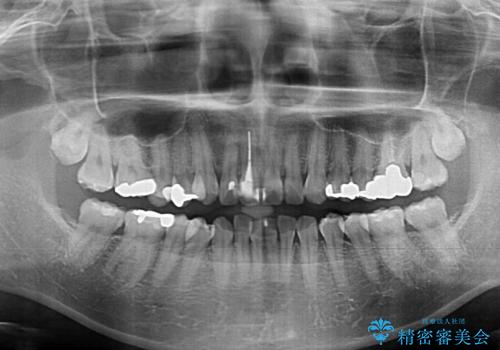

- 前歯のデコボコを治したいとのことで来院された患者様です。

上下顎ともに歯列全体の後方移動とIPR(歯と歯の間を削る)によってデコボコが解消するように設計し、インビザラインにより治療を行うこととしました。